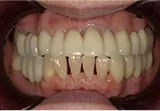

| 年齢/性別 | 70代女性 |

| 主訴 | 左下奥歯に痛みがある、全体的に治したい |

| 治療内容 | 全体的に歯周病やむし歯、根の治療を行い、仮歯を使用して咬合治療を実施。左上、右下、左下の計3本を抜歯し、右上には2本のインプラントを埋入しました。 |

| 治療期間 | 4か月(インプラントのみ) |

| 費用 | 1,116,500円税込 |

| リスク・副作用 | 炎症反応によって術後に腫れや副鼻腔炎が生じることがあります。その程度は、手術の範囲や方法によって異なりますが、多くの場合、時間の経過とともに徐々に治まります。 |